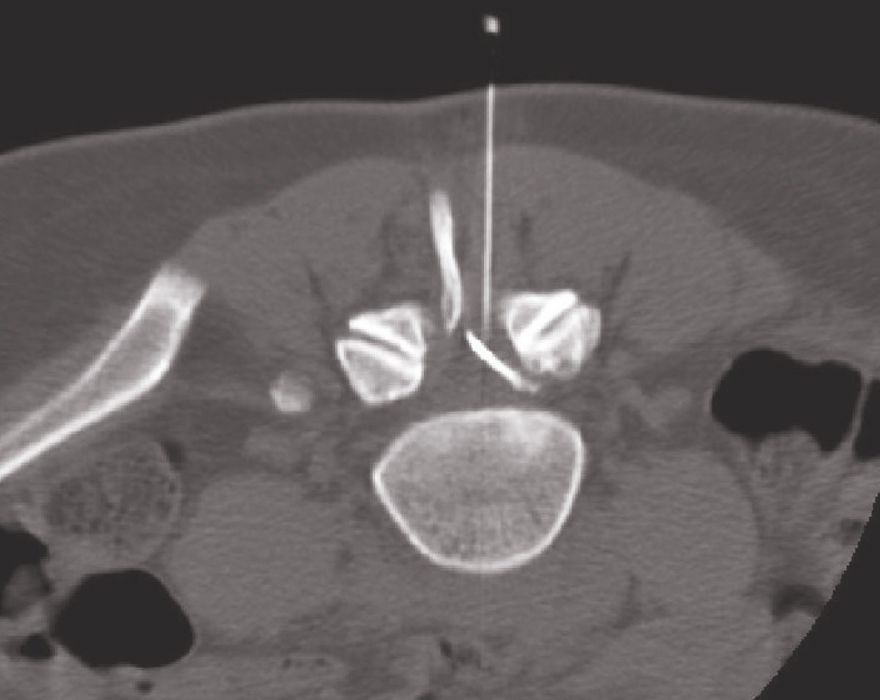

Periradikuläre Therapie (PRT) Dr. Daniel NiehuesPaas Praxisvertretung Orthopädie. Diese Krämpfe sind jetzt in den 7 Wochen nach der letzten Spritze etwas weniger. Bandscheibenvorwölbung an der HWS und zum Glück nur die "Vorstufe" zum Bandscheibenvorfall an der LWS (Lumbago)

CT gesteuerte Schmerztherapie. Momentan nehme ich Tilidin 50/4 Tabl und zur Ergänzung noch Tilidin Tropfen gegen den Schmerz.Gehen geht nur mit Rollator Schlingentisch und Strom / Wärme hat nicht gerade viel gebracht bislang (allerdings war ich auch erst 4 mal dort)..